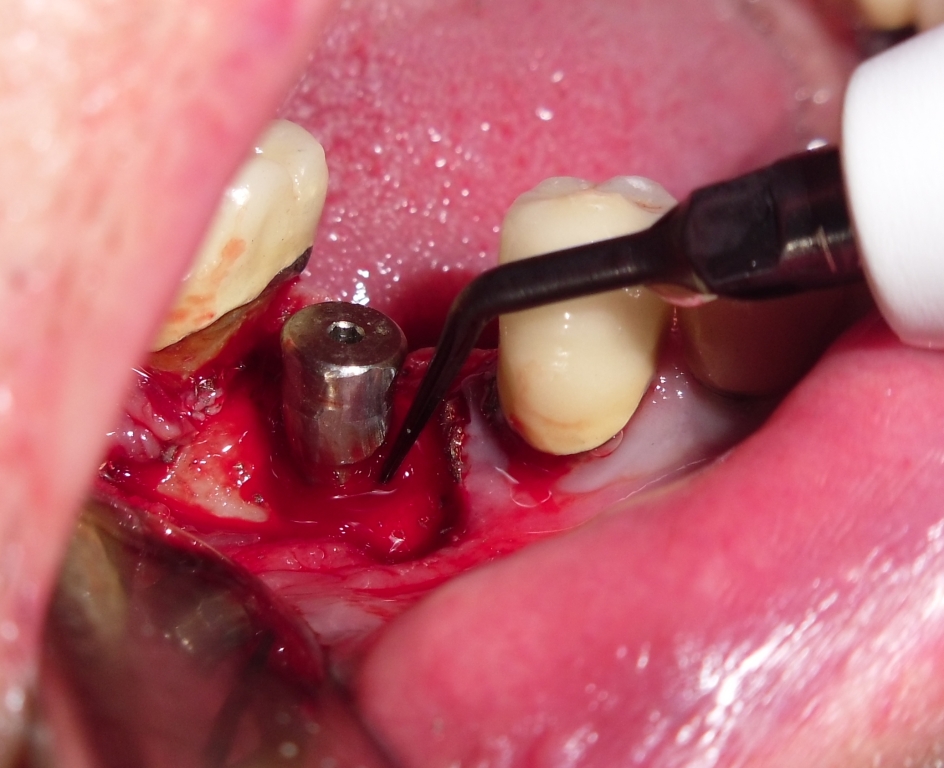

Debridement del difetto mediante strumenti manuali e ultrasonici con inserti dedicati e decontaminazione della superficie implantare  mediante applicazione topica di Ambramicina

post-109-13532628040_thumb.jpg

post-109-13532628051_thumb.jpg